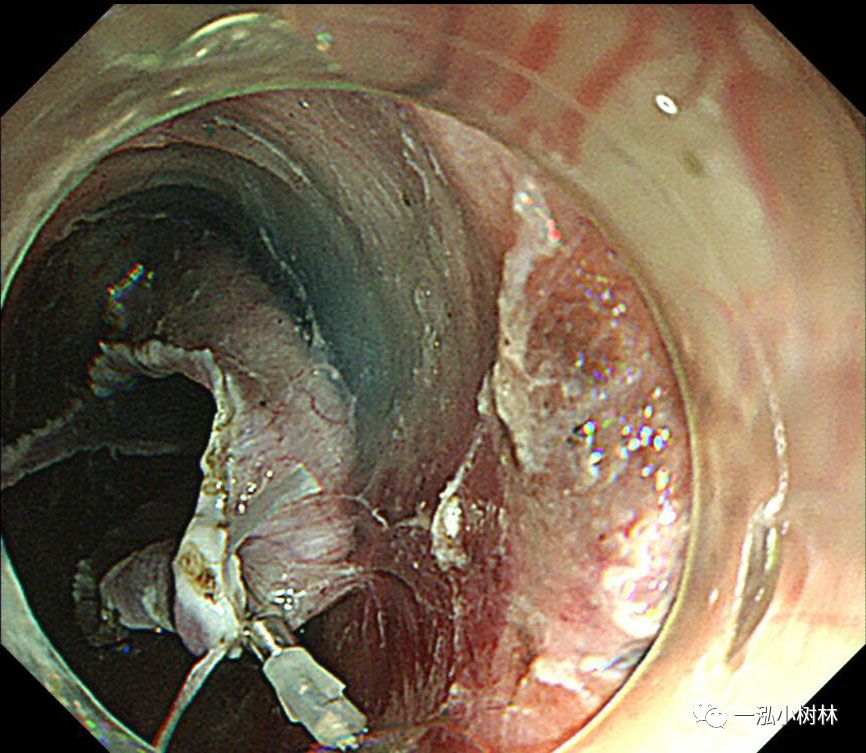

图4 用Dual刀在病变外5mm处标记

图5 在近端(口侧)进行黏膜切口